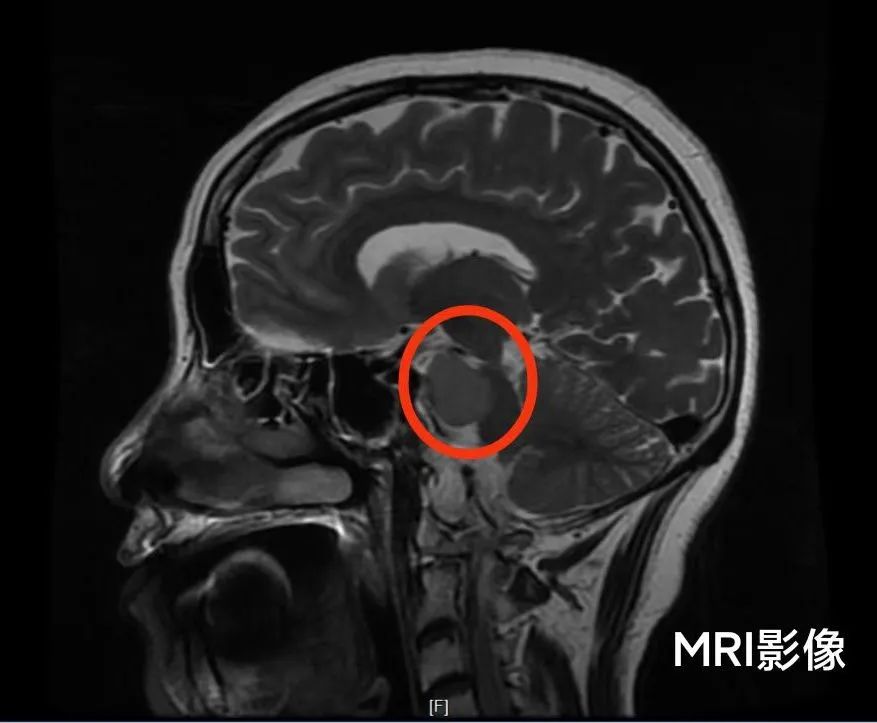

患者柳女士(化姓)半年前出现右侧面瘫,多方治疗后效果甚微。后来到新乡二院进一步检查头颅MRI平扫+增强提示:右侧岩斜区占位,脑膜瘤可能。柳女士辗转找到该院副院长神经外科主任简国庆教授,简院长接诊后发现,柳女士的肿瘤位置很深且紧靠脑干、椎-基底动脉、动眼神经、面听神经、三叉神经等重要结构,手术难度及风险极大。

简院长介绍:“岩斜区”是一个解剖名词,岩是岩骨,斜是斜坡。这个区域的肿瘤是所有颅脑肿瘤里面极其复杂的,因其位置较深,且肿瘤前方的岩骨和斜坡两块骨头缝里面穿行许多的神经和血管,最常见的就是动眼神经、滑车神经、三叉神经、面听神经、后组颅神经等重要的面部神经,而肿瘤后方就是人的生命中枢“脑干”,脑干很多的供血动脉及回流静脉都可能与肿瘤紧密粘连,甚至从肿瘤中穿行。该区域的脑肿瘤切除手术的并发症也相对多且严重,甚至可能会出现术后患者长期昏迷、气管插管等风险。因此该区域的手术对医生的解剖知识,高超的手术技能(如镂空技术、蜕膜技术等),精密的手术器械,手术显微镜,术中电生理检测等一些高端设备及人员配合要求极高。